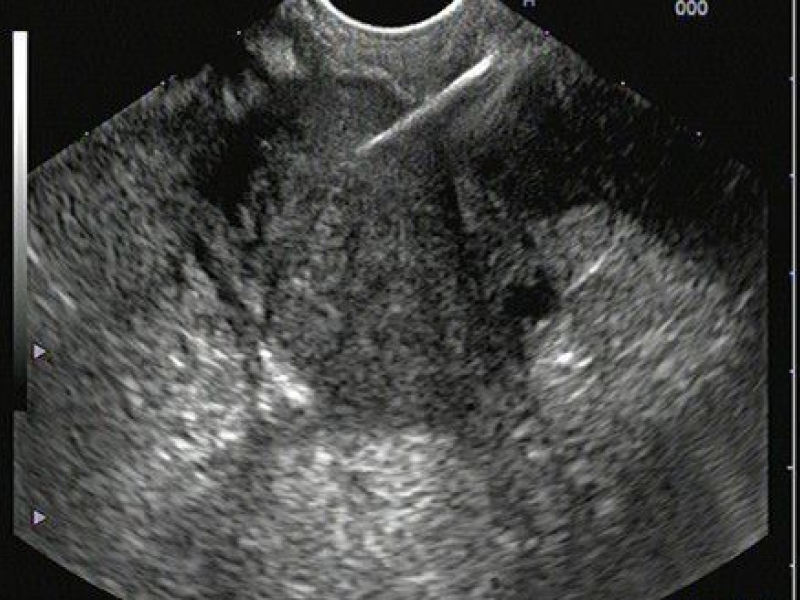

Ecoendoscopia

Ecoendoscopia alta e baixa

Combinação de endoscopia e ultrassom para diagnósticos profundos e biópsias guiadas de alta precisão.